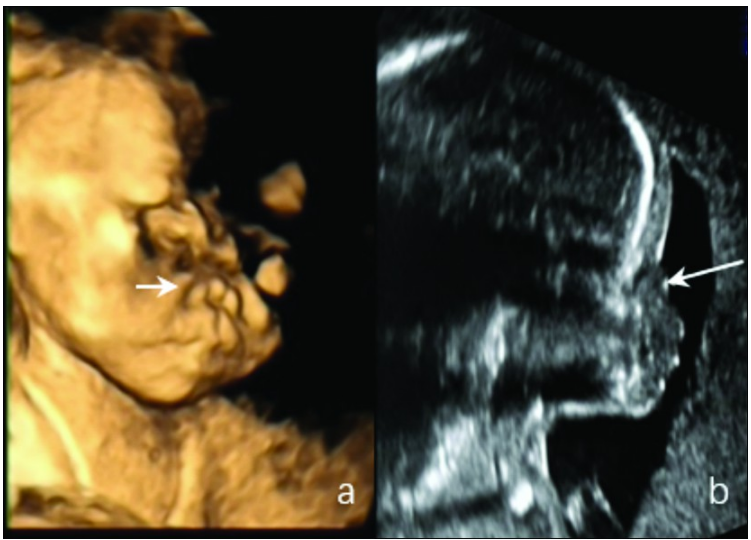

孕妇26岁,孕2产0。孕妇父母为近亲结婚。孕22周3天在复旦大学附属妇产科医院行超声大畸形筛查提示:胎儿鼻骨缺失,鼻部软组织扁平,椎管狭窄

——遗传综合征可能,见图1。

图1 胎儿点状软骨发育不良的表现。a.三维超声胎儿鼻部软组织扁平;b.二维超声胎儿鼻骨缺失。